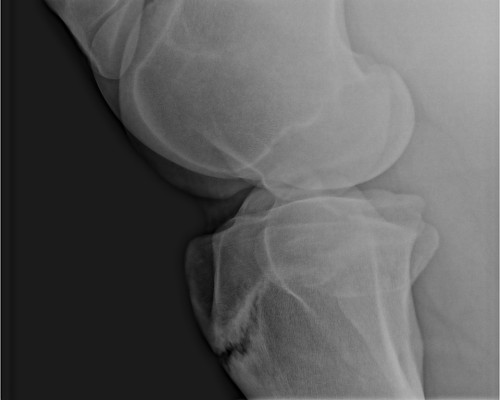

Can you just give me your opinion of what this image discloses?

The reason I ask is b/c the vet that took the film says it's a growth plate (the horse pivoted or something just as she tooke the image) and another vet says it is a fractured tibia....

The horse is a 2 1/2 year old Canadian warmblood filly.

No, there is absolutely no lameness nor swelling. The vet that did the prepurchase and about $1200 worth of slides said how lovely she moved. She maintains it is nothing more than a growth plate. But when I asked another opinion and was told it was a proximal fracture of the tiba, welll...now I am completely confused, who do I believe? Everything else on this horse checks out 100%.

The problem Sherri is that there is overlap between the appearance of normal and abnormal growth plates in the growing horse: normal nonclosed growth plates can look like non-displaced fractures. The radiograph cannot answer the question of whether there is such a nondisplaced fracture or not. But what is not as questionable is whether a fracture of the growth plate causes lameness. A fracture that did not cause lameness would be an unusual case indeed.

The filly has been deemed sound by a couple more lameness vets that looked at the radiograph and because of her age and the fact that she is completely sound, no lameness whatsoever, they say it is normal growth plate.

how about looking at the other side for comparison and education? That's what I do with most kids under 13 to look at the growth plate vs. injury vs. injured growth plate challenge...